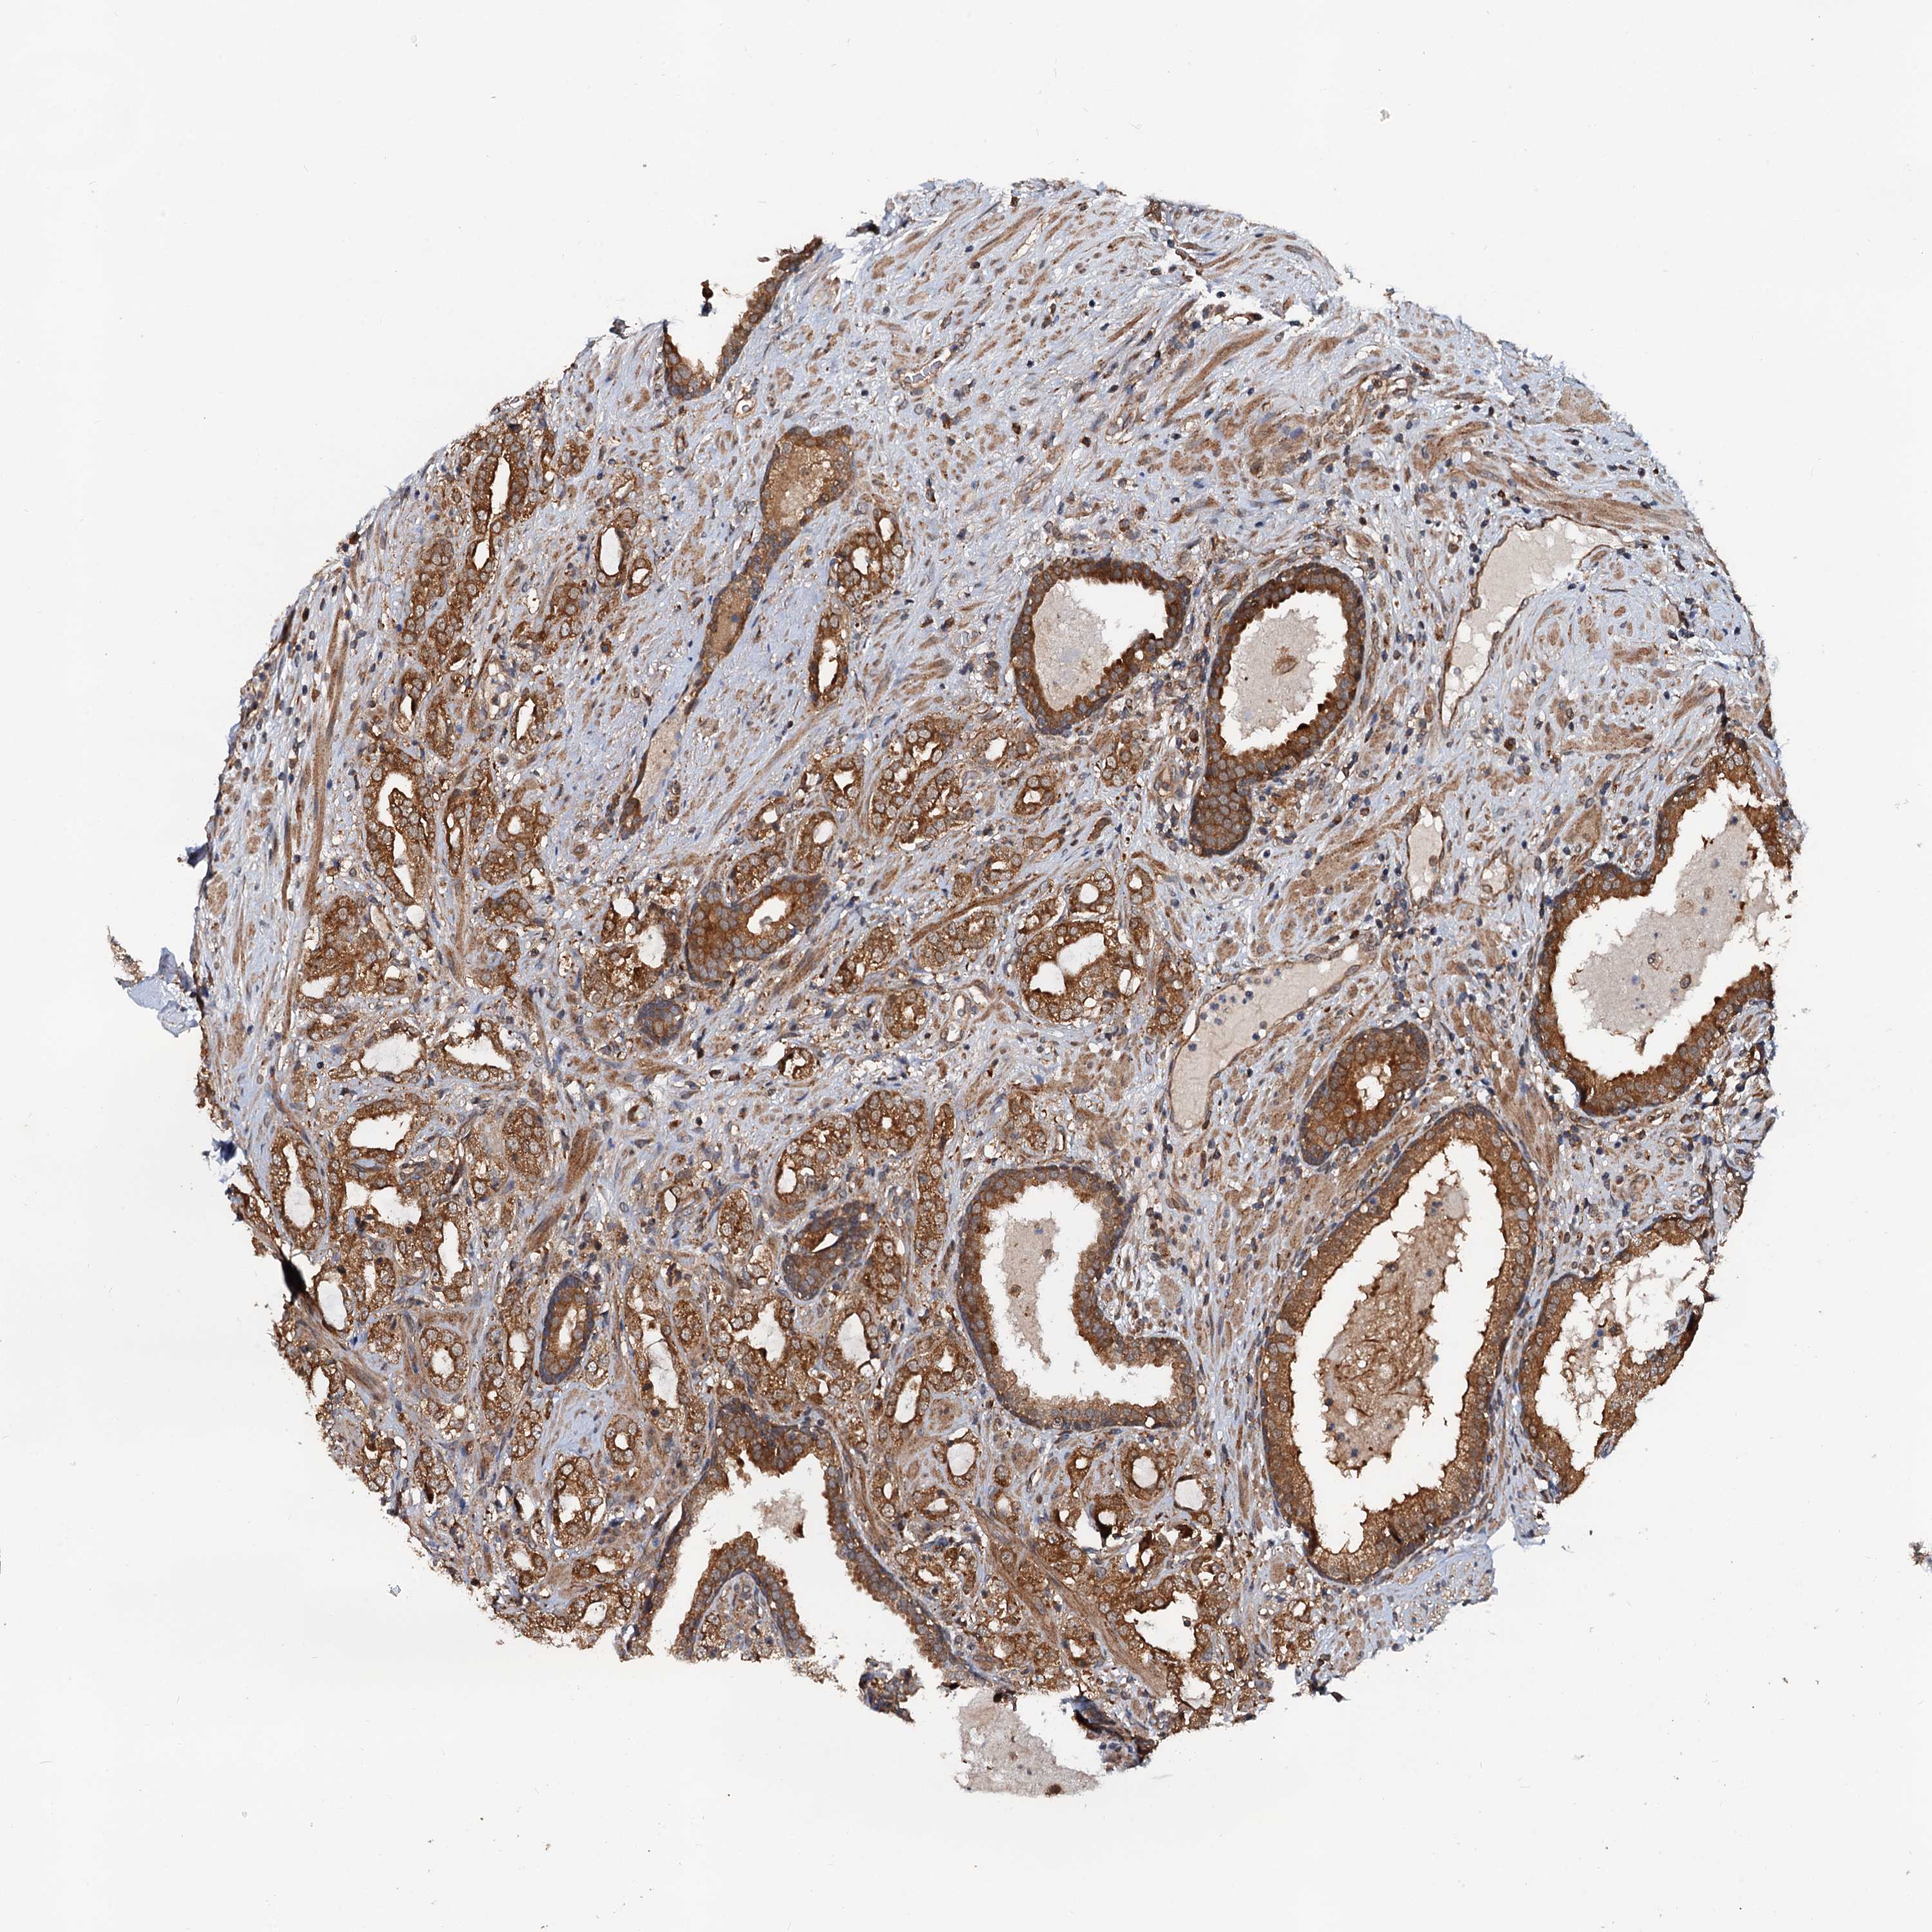

PROSTATE CANCER - Protein expressioni

A mouse-over function shows sample information and annotation data. Click on an image to view it in a full screen mode. Samples can be filtered based on level of antibody staining by selecting one or several of the following categories: high, medium, low and not detected. The assay and annotation is described here.

Antibody stainingi

Antibody staining in the annotated cell types in the current human tissue is reported as not detected, low, medium, or high, based on conventional immunohistochemistry profiling in selected tissues. This score is based on the combination of the staining intensity and fraction of stained cells.

Each image is clickable and will lead to virtual microscopy that enables deeper exploration of all samples and also displays staining intensity scores, fraction scores and subcellular localization as well as patient and tissue information for each sample.

Antibody HPA039371

Antibody HPA040174

Staining

High

Medium

Low

Not detected

Intensity

Strong

Moderate

Weak

Negative

Quantity

>75%

75%-25%

<25%

None

Location

Nuclear

Cytoplasmic/membranous

Cytoplasmic/membranous,nuclear

Adenocarcinoma, NOS

Adenocarcinoma, High grade

Adenocarcinoma, Low grade